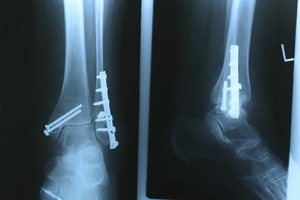

Common symptoms of stress fractures are pain and swelling near the weight bearing area on the injured bone. When initial x-rays are performed, it is possible that the fracture will not show up. However, once the stress on the area continues, the damage will increase, and the fracture will be severe enough to show up on an x-ray. Certain parts of the foot are more likely to develop stress fractures than others. Areas that typically have these fractures are: the metatarsals, the navicular bone, the calcaneus, tibia, and fibula.